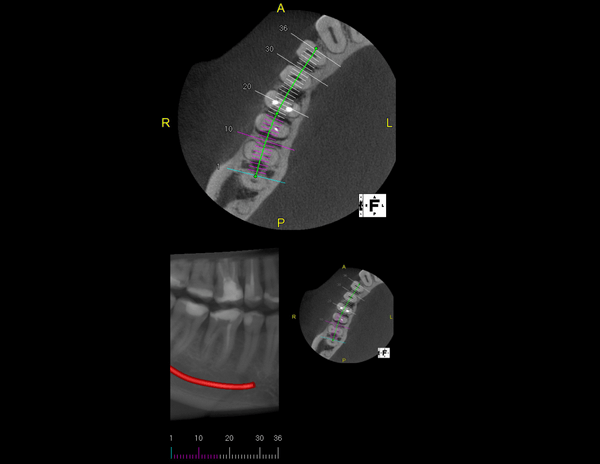

A Tomografia Computadorizada pela técnica do feixe cônico/cone beam (CBCT) introduziu um novo conceito de tomografia computadorizada na região bucomaxilofacial, que por meio da rápida aquisição volumétrica produz imagens com altíssimo grau de definição e fidelidade, além da redução na dose total de radiação emitida ao paciente.

Além disso, ocorre a minimização dos artefatos de imagem em relação à TC médica, o que torna possível a realização de imagens com qualidade diagnóstica e precisão sub-milimétrica, mesmo na presença de estruturas metálicas (restaurações, pinos/núcleos, aparelhos ortodônticos).